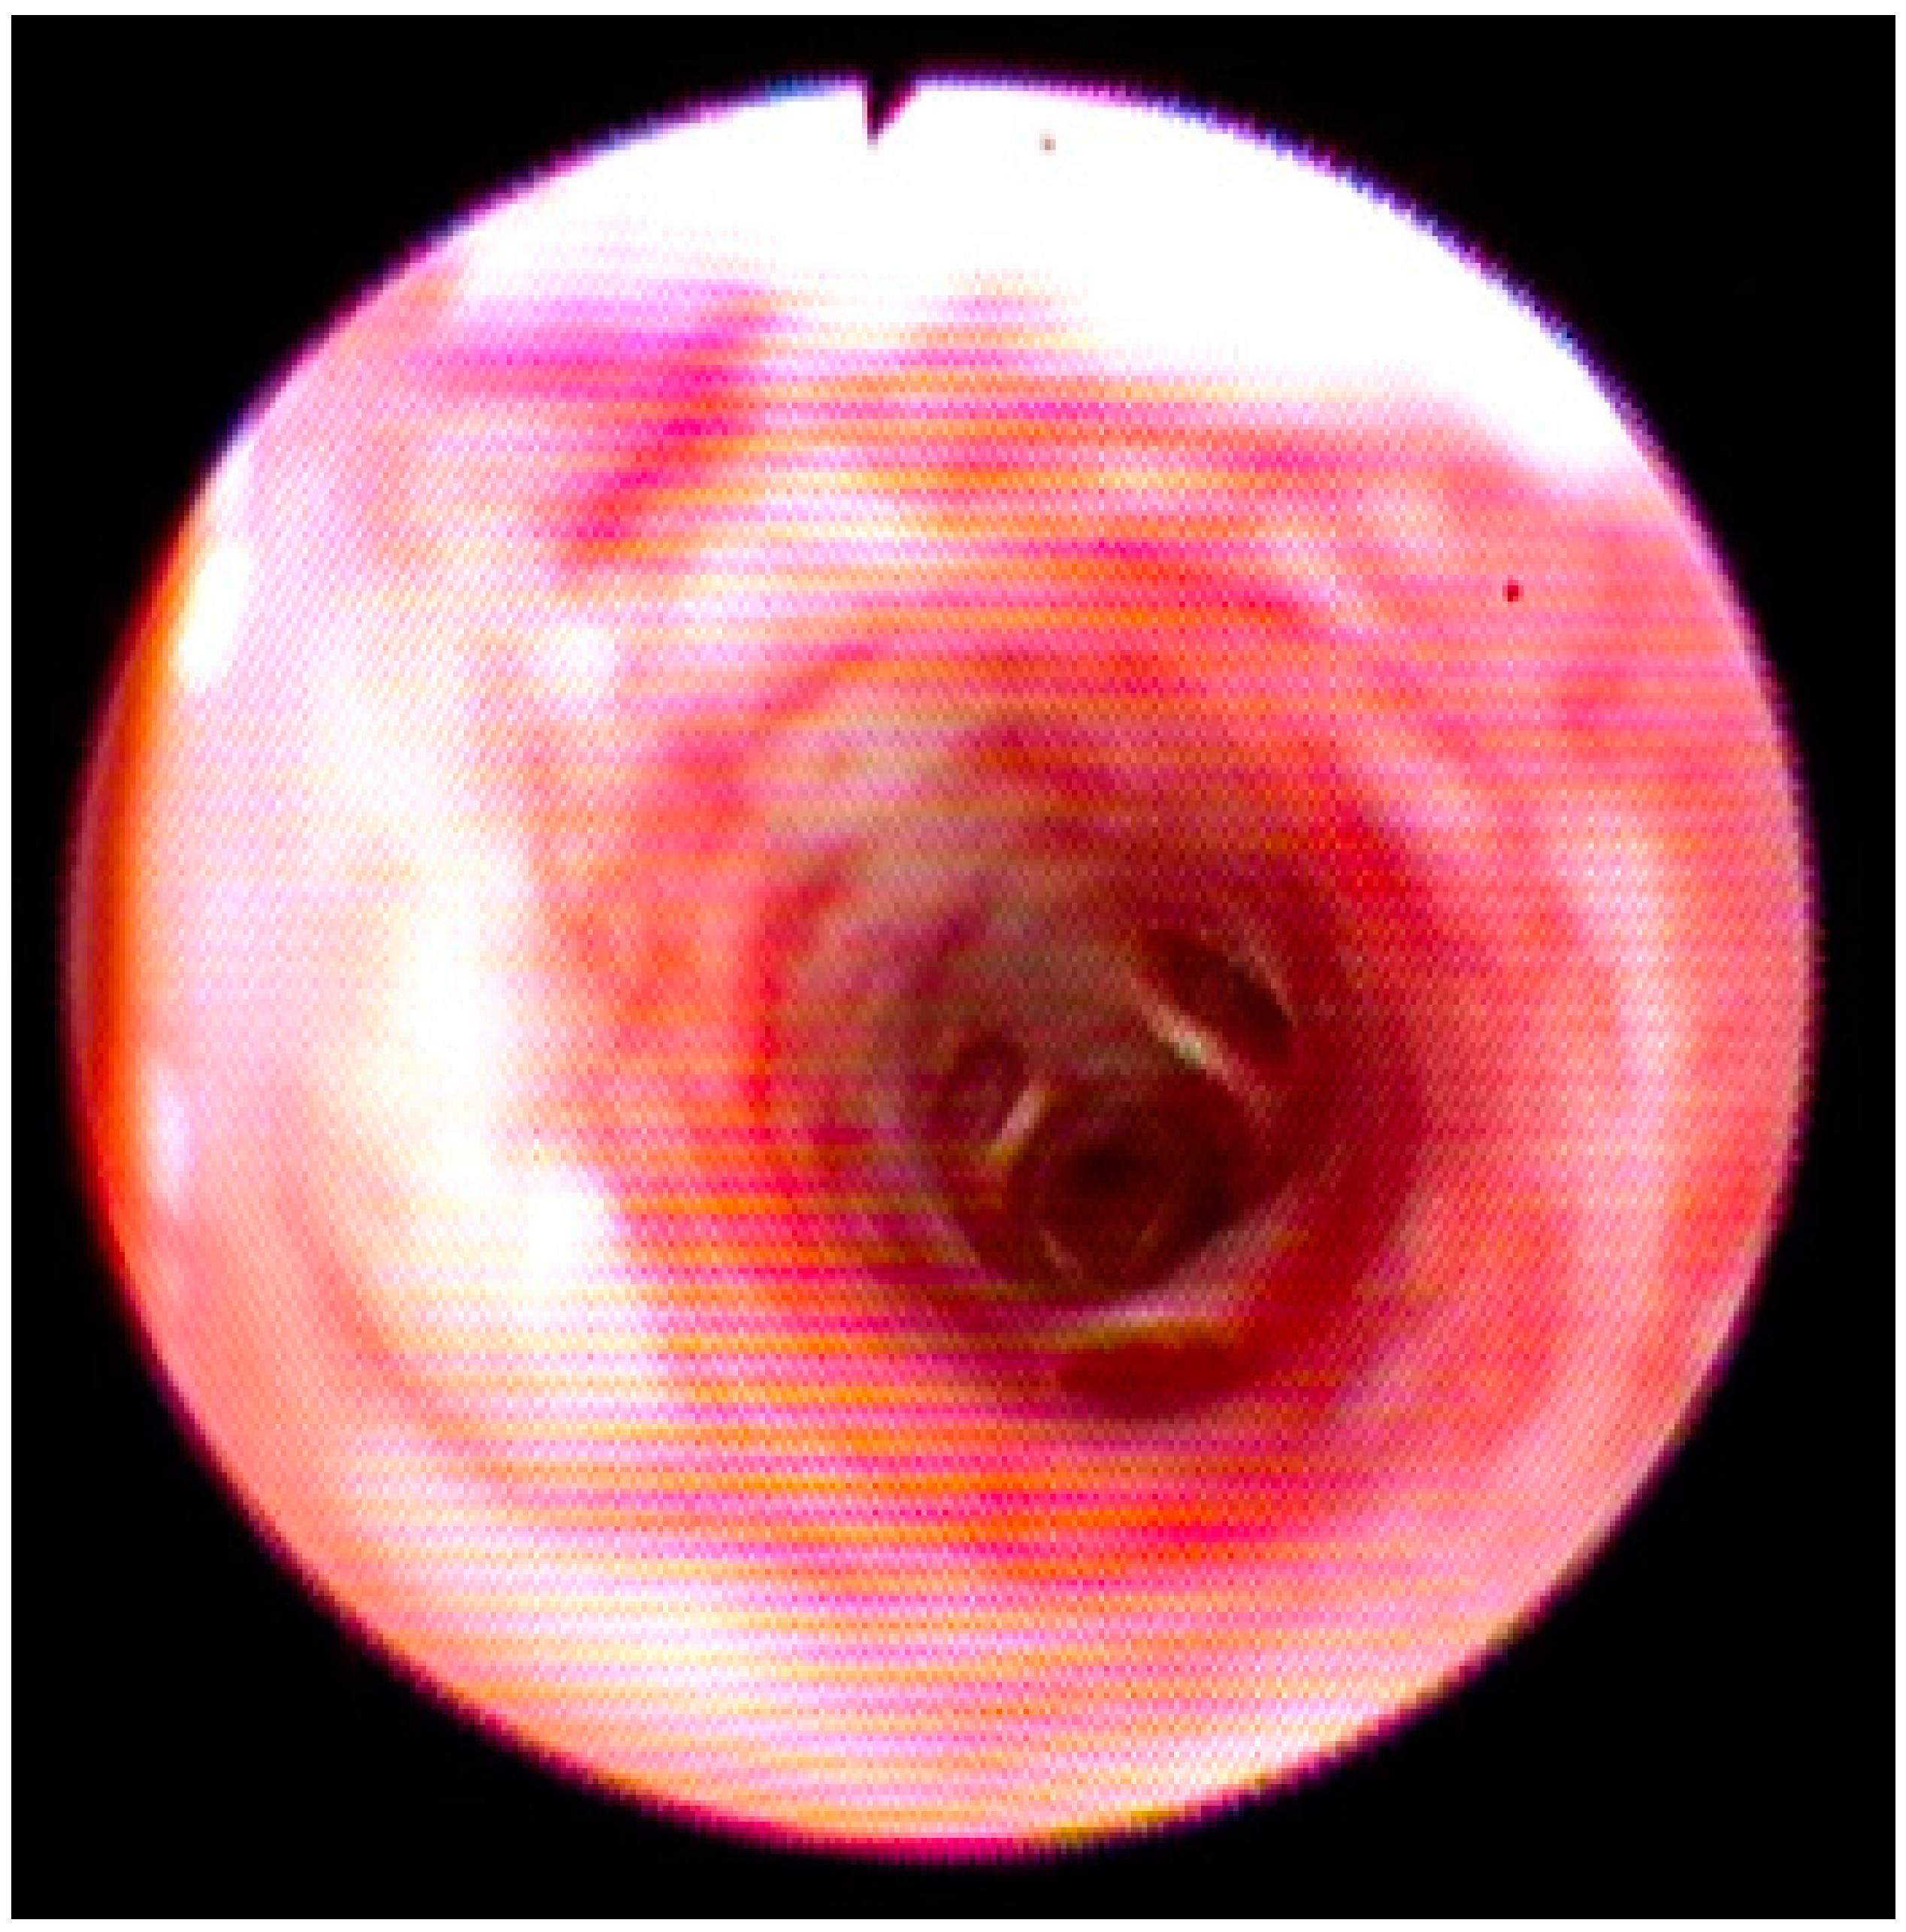

During endoscopic examination, a diffuse edema and congested mucosa from the larynx to the trachea and bronchi were observed. Moreover, an increase in the vascular texture that was widespread, especially in the bronchi, without the presence of exudate was detected (Figure 2).

Figure 2. Endoscopic view of the principal broncho with congested mucosa without exudate.